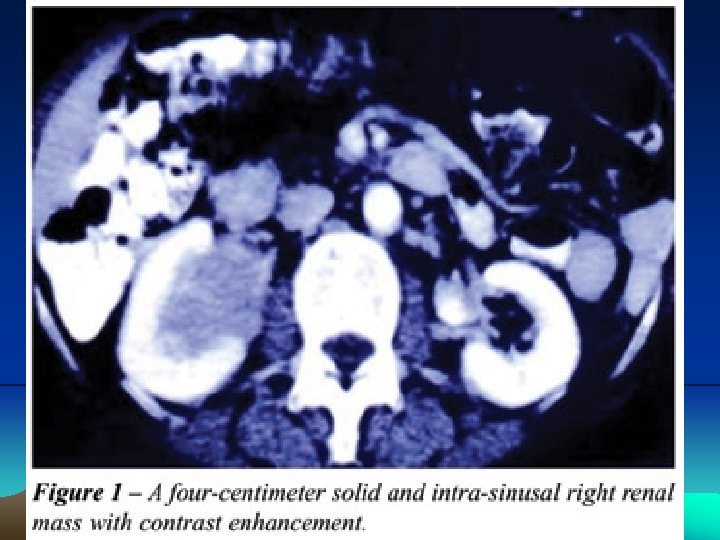

Renal lymphoma has an insidious clinical presentation that occurs late in the course of the disease. It can present in many ways, however the most common are primary tumors presenting single or multiple nodules, or that involve the kidney, either in a hematogenic dissemination form or through a contiguous retroperineal disease

Primary renal Iymphoma